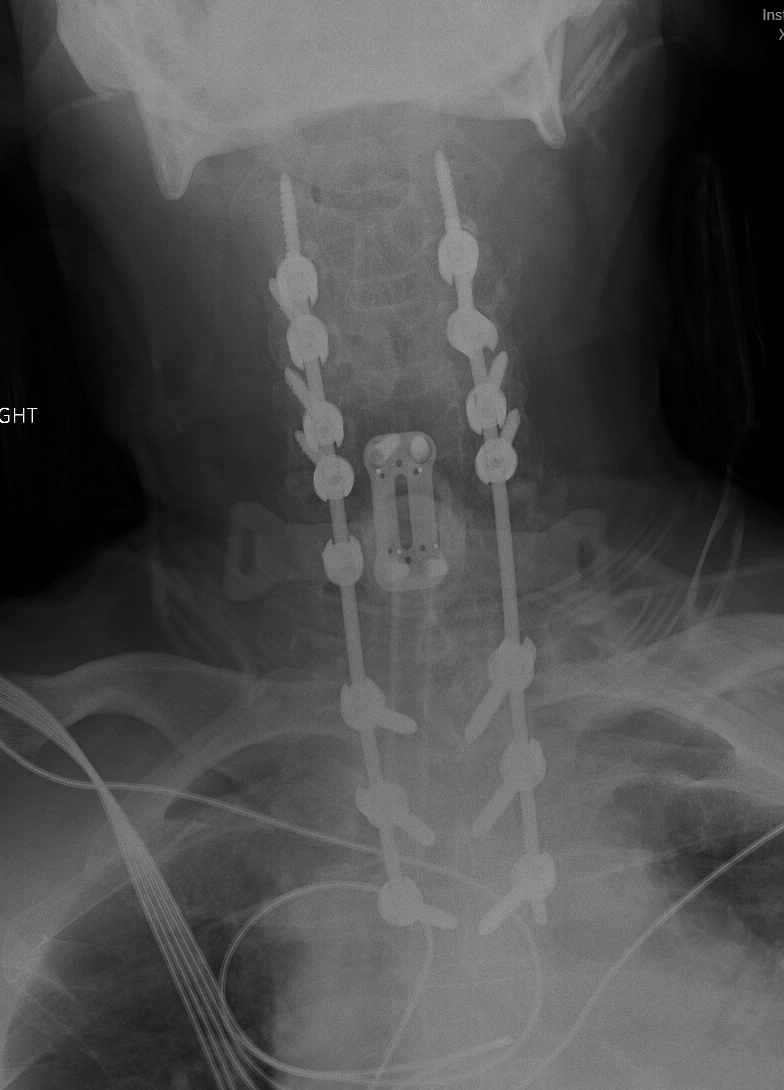

Cervical Spine Revision Surgery

Revision of a cervical spine surgery can be needed for a variety of reasons: failure for bones to fuse (cervical pseudoarthrosis), malposition or failure of implanted hardware, inadequate decompression of the spinal cord or nerve roots, new or persistent neck pain or cervical radiculopathy or myelopathy symptoms, degeneration of neighboring spinal segments, infection, spinal instability, and others.

Management options for a failed cervical surgery might include ACDF, cervical corpectomy, CORUS cervical fusion, or posterior cervical fusion, among others. Each of these options has benefits and drawbacks. The right surgery for you will depend on your symptoms, your previous surgery, the number of spinal levels affected, and factors related to your medical history, age, smoking status, and spinal anatomy.